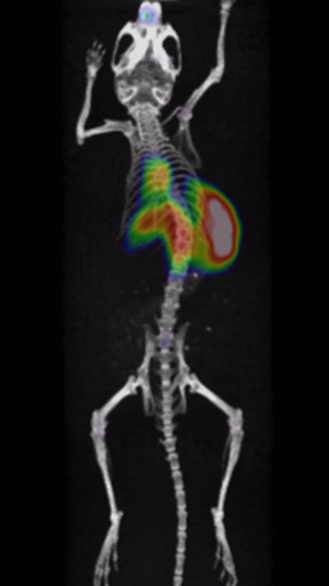

Through quality and process explorations with Zr-89-marked antibody conjugates, highly emissive-pure radiodiagnostic drug molecules are obtained and supplied for preclinical animal imaging and biodistribution studies, as well as subsequent IIT imaging in the clinic.

Rapid validation of Zr-89-marked antibodies

Fast lesion cumulation, most efficient distribution and high targeting ability for xenotransplanted tumor models.